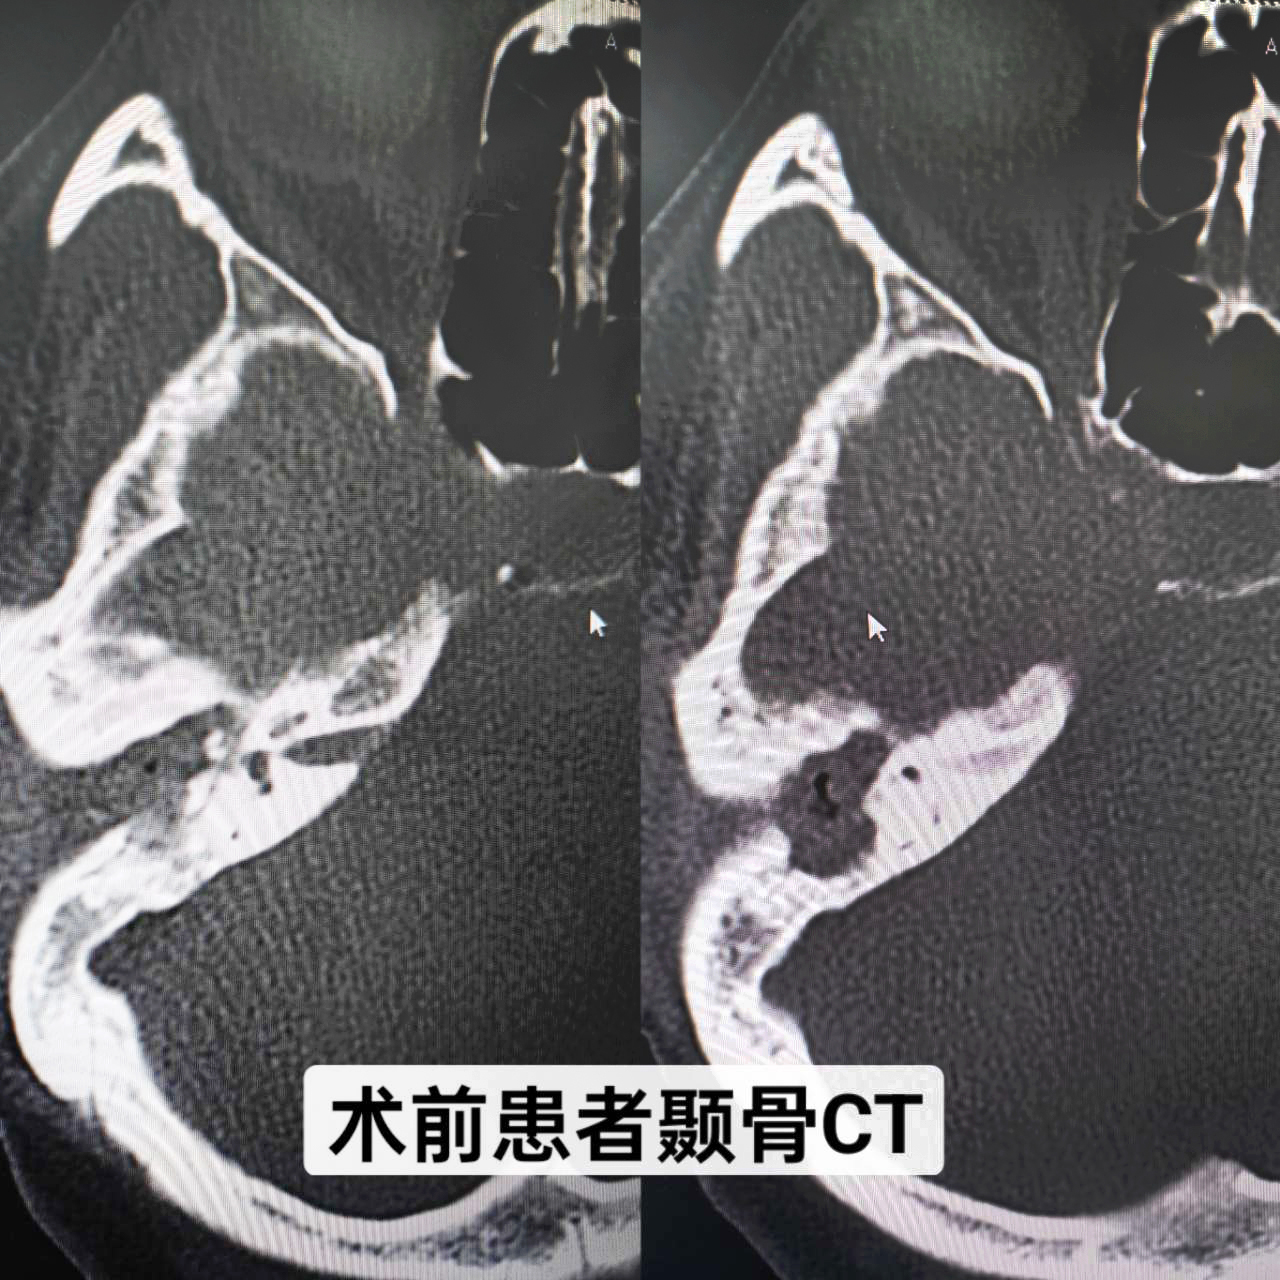

患者,女,34歲,幼兒時發(fā)生過中耳炎,經(jīng)治療后已明顯好轉(zhuǎn),但最近一個月反復(fù)右耳腫痛、流膿、流水,伴聽力下降,嚴(yán)重影響生活,來我院就診。耳內(nèi)鏡示:右耳外耳道縮窄,肉芽組織及膿血性分泌物填充,鼓膜窺不及;顳骨CT示:右側(cè)中耳鼓室擴大,見軟組織影填充并向外耳道延伸,右側(cè)聽小骨骨質(zhì)吸收,形態(tài)小,部分聽骨欠清,考慮:右側(cè)膽脂瘤型中耳炎(累及右側(cè)外耳道)。耳鼻咽喉科副主任顏抗經(jīng)過閱片及結(jié)合患者病史,判斷患者是中耳膽脂瘤造成聽小骨斷裂,建議患者入院手術(shù)治療。